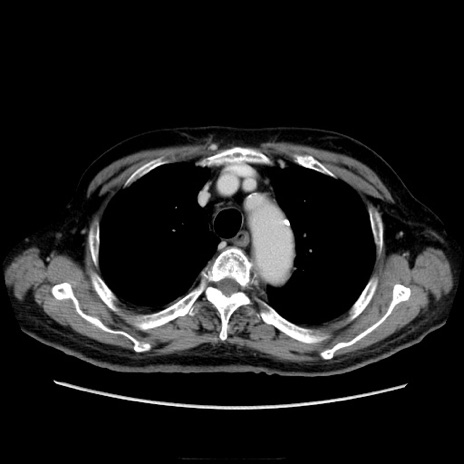

症例21(横断像)

【症例】70歳代男性

【主訴】腹痛

【現病歴】肝硬変・肝細胞癌にてかかりつけの方。約9時間前に食後より腹痛出現。症状が徐々に増悪し、嘔吐出現したため来院。

【既往歴】肝硬変、肝細胞癌(RFA、TACE後)

【身体所見】意識清明、表情苦悶様、BT 36℃、BP 129/78mmHg、P 88bpm、SpO2 97%(RA)、右上腹部から心窩部にかけて圧痛あり、反跳痛なし、筋性防御あり。

【データ】WBC 5800、CRP 0.16